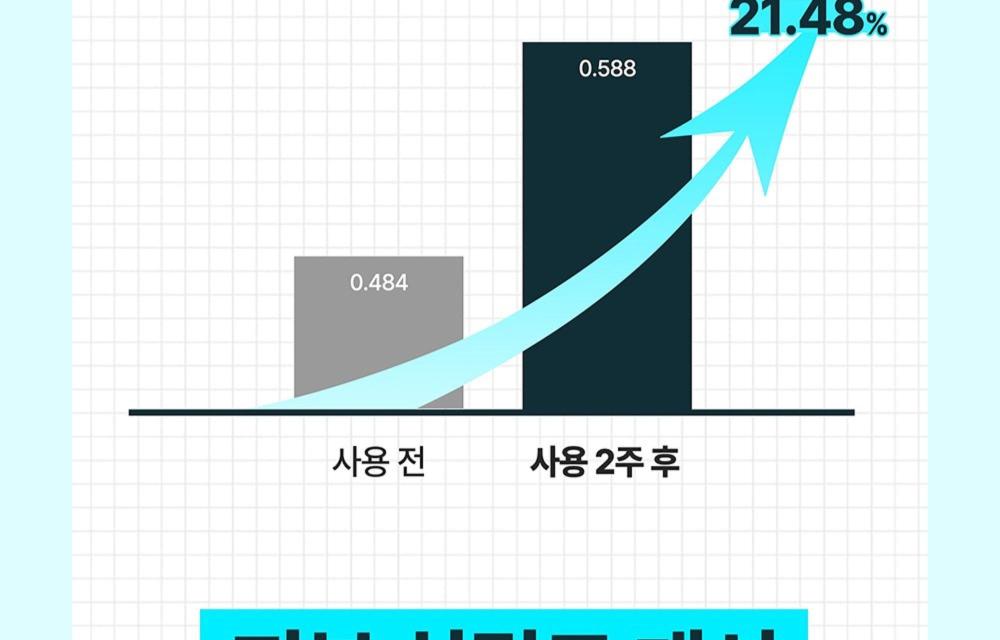

可見效果

- 僅 2 週使用,即可感受由內而外的緊緻水潤光澤肌膚。

- 「皮膚 plumping(豐盈)效果之人體適用試驗」。